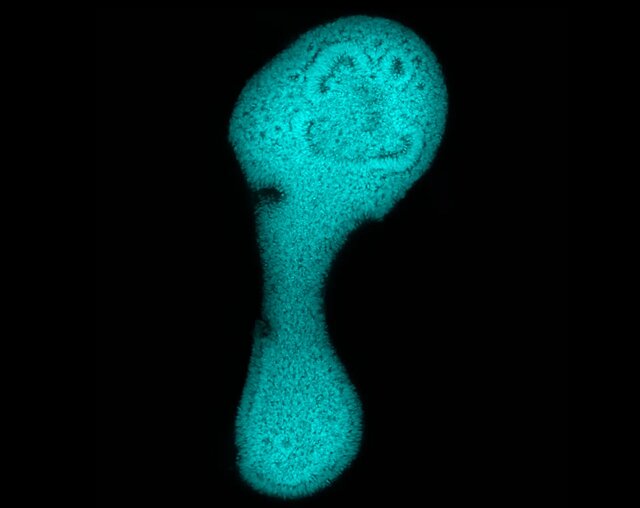

این یک ارگانوئید محوری خودسازماندهی شده است که به طور قابل توجهی کشیدگی لوله عصبی را نشان میدهد.

تصویر از: محمد شاکر

علم ارگانوئید شامل کشت نسخههای مصنوعی کوچک از اندامهای داخلی فرد برای تحقیقات بر روی داروها و بیماریها میشود. این ارگانوئید از نخاع انسان، تفکیک جوامع سلولی را نشان میدهد که به نورونها و نورونهای حرکتی تبدیل میشوند.

تصویر از: شان موریسون(Sean Morrison)